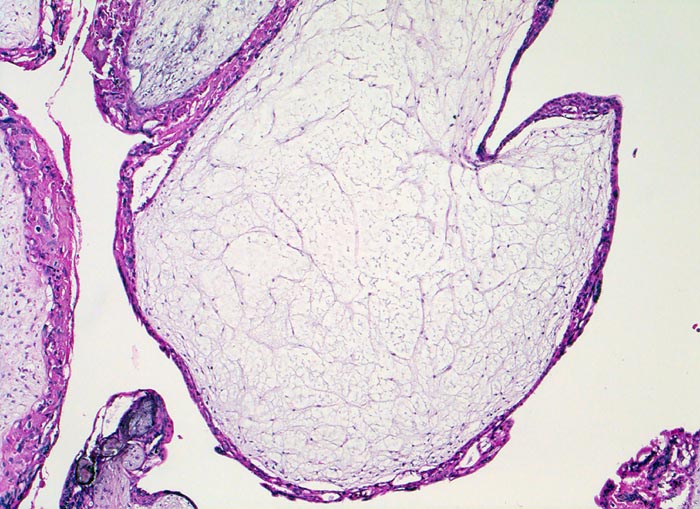

PathoPic ID 5124 - Blasenmole

Blasenmole

angeboren /genetisch/Missbildung

Abortmaterial

Paidopathologie

Die Plazentarzotten sind aufgetrieben, das Stroma ist ödematös und enthält keine Gefässe. Das Trophoblastepithel ist verdickt (normal zweilagig).

beta HCG Level von 150'000 mIU/mL. Uterus zu gross für das Gestationsalter von 10 Wochen. Arterielle Hypertonie.

Histologie

50